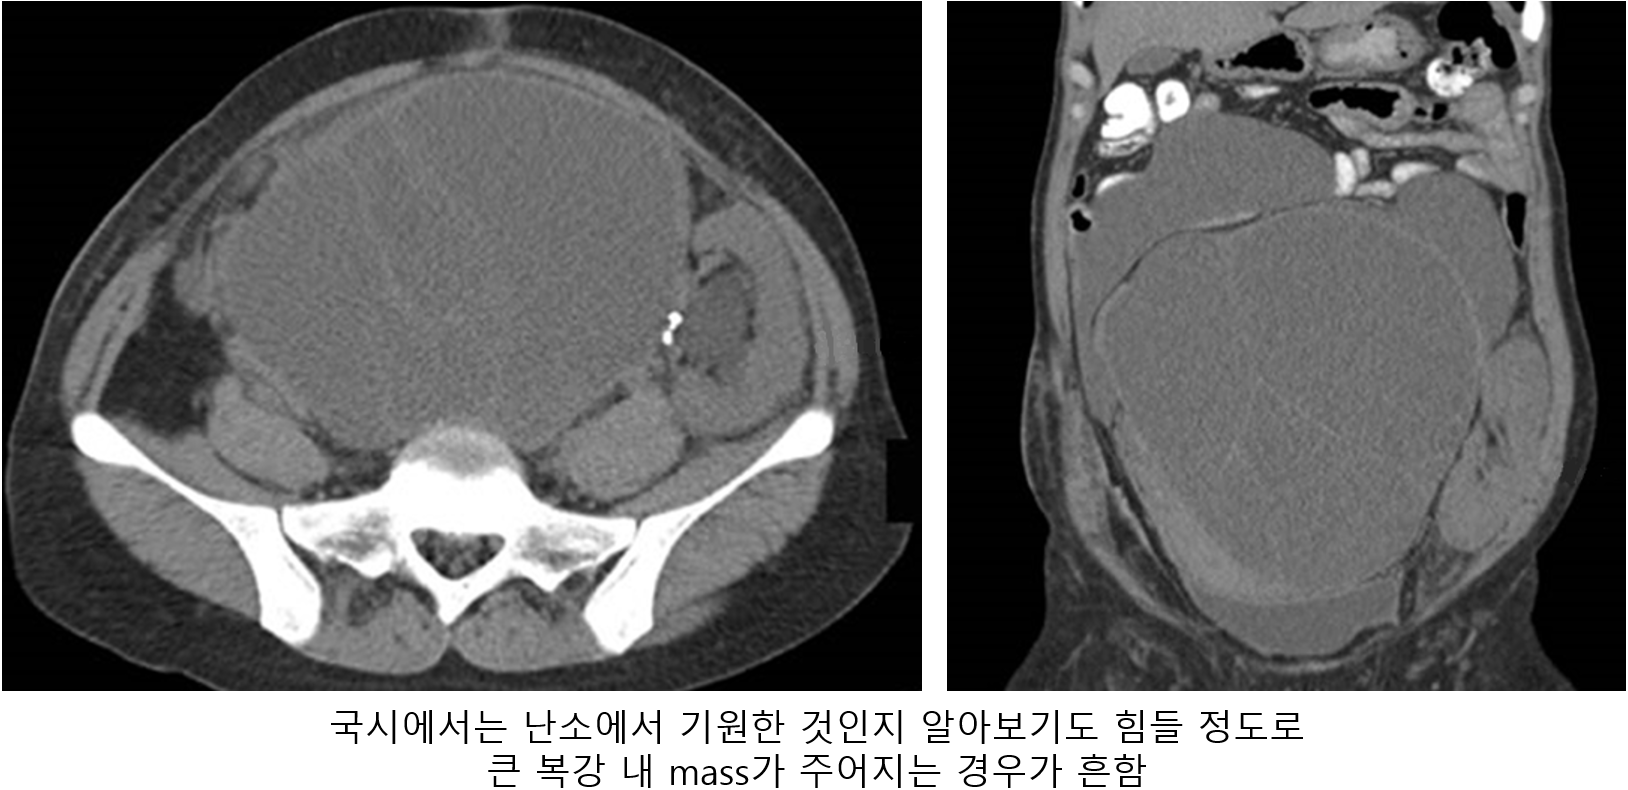

1) 복부 CT/MRI, PET scan: 난소암 자체의 진단보다는, 복부/골반의 침범 범위를 확인하는 목적